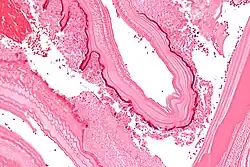

Larval/hydatid cyst stage

From the embryo released from an egg develops a hydatid cyst, which grows to about 5–10 cm within the first year and can survive within organs for years.[25] Cysts sometimes grow to be so large that by the end of several years or even decades, they can contain several liters of fluid. Once a cyst has reached a diameter of 1 cm, its wall differentiates into a thick outer, non-cellular membrane, which covers the thin germinal epithelium. From this epithelium, cells begin to grow within the cyst. These cells then become vacuolated and are known as brood capsules, which are the parts of the parasite from which protoscolices bud. Often, daughter cysts also form within cysts.[24]

The cysts found in those with cystic echinococcosis are usually filled with a clear fluid called hydatid fluid, are spherical, typically consist of one compartment, and are usually only found in one area of the body. While the cysts found in those with alveolar and polycystic echinococcosis are similar to those found in those with cystic echinococcosis, the alveolar and polycystic echinococcosis cysts usually have multiple compartments and have infiltrative as opposed to expansive growth.[11][12]